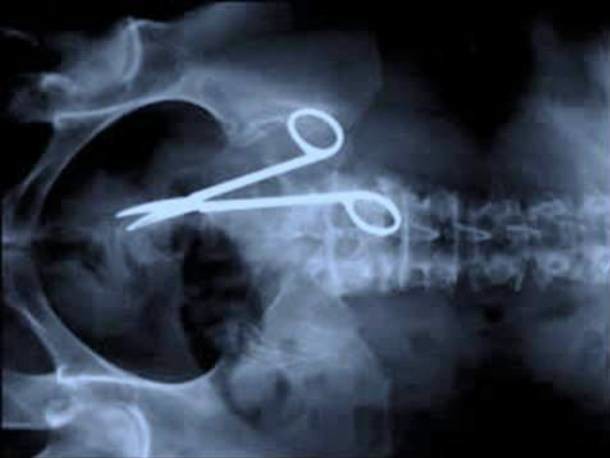

En los hospitales y clínicas hay todo tipo de emergencias, sin embargo, algunas de ellas pueden ser verdaderamente perturbadoras, sobre todo porque las personas encuentran constantemente nuevas y creativas maneras de hacerse daño. En esta galería conocerás algunas.